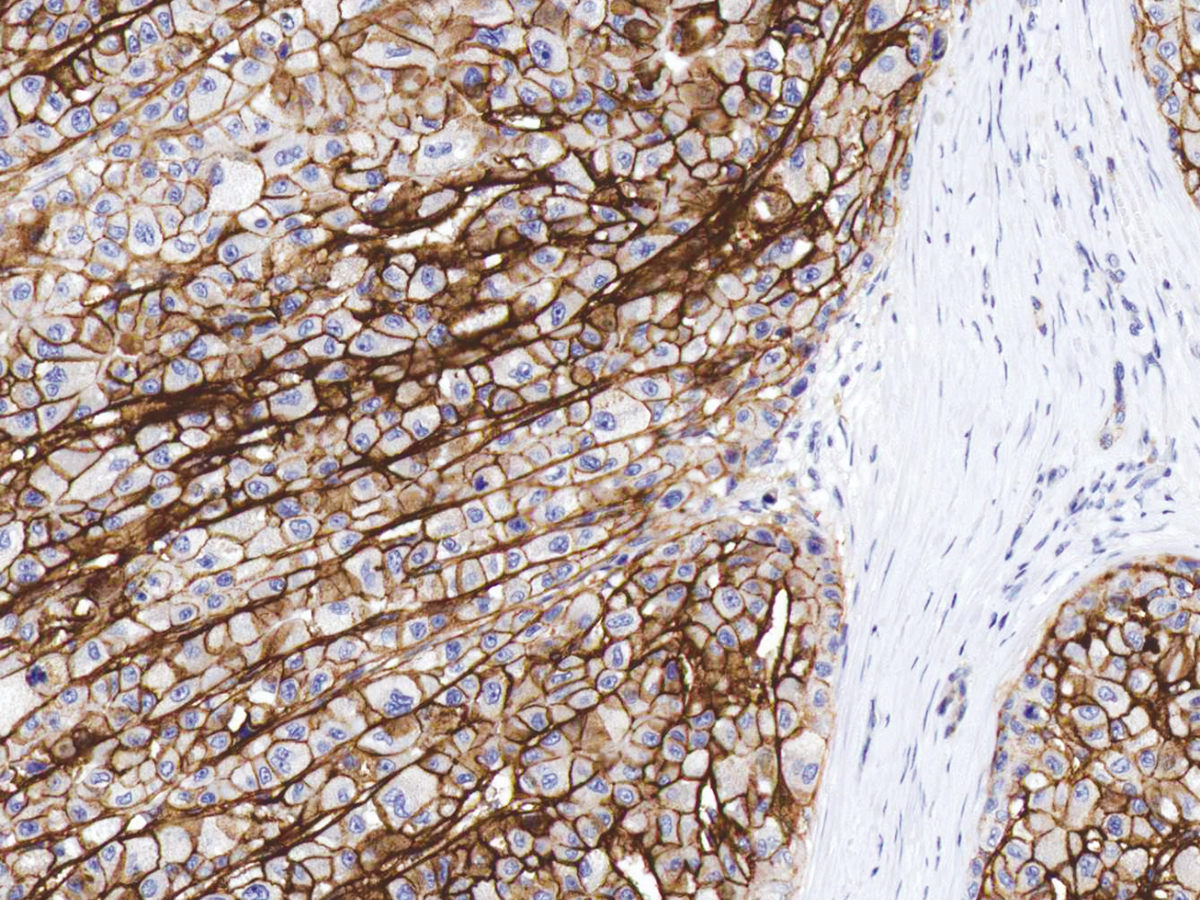

图片:

CD138 [P1037] on Liver Cancer